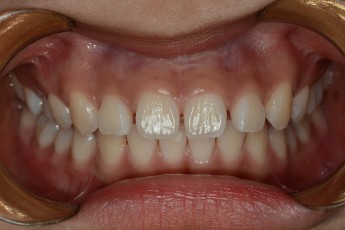

BEFORE & AFTER